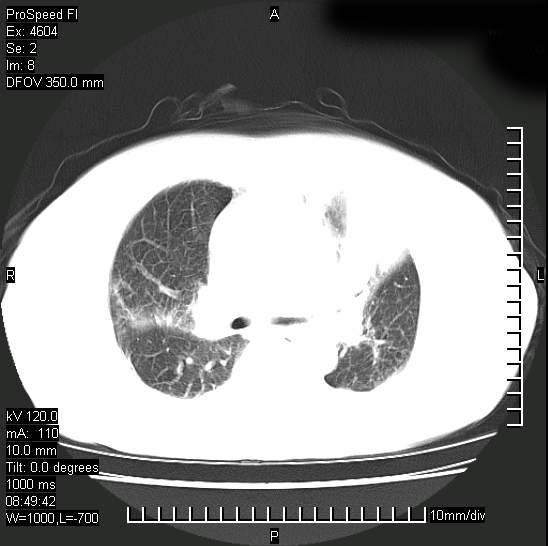

标题: CT15528:女性,79岁,近几日晚上高热,39度,仍咳少量血

十几年前曾患肺结核,一周前突咳血约100ml,中性粒细胞稍高,诊断两上肺陈旧结核,下肺炎症,给予抗炎治疗,近几日晚上高热,39度,仍咳少量血,4天前ct及今天ct上传。

[face=黑体]8月30日[/face]

支持陈旧性肺结核并两下肺感染,两侧胸腔积液。

短短几天内,病变范围明显增多扩大,以左侧明显,而且双侧出现胸水,还是考虑感染.

支持  结核ban感染,节段性肺不张,支气管内膜结核可能

继发性结核感染加重。左侧合并有支气管内膜结核。

1)两肺结核并感染。2)不排除左肺上叶中央型肺癌并阻塞性肺炎、肺不张可能;建议行纤支镜检查。3)右肺门及纵隔淋巴结肿大。4)双侧胸腔积液。

陈旧性肺结核及左下肺不张,咯血后肺部感染,双胸腔积液,高热可能与痰液引流不畅有关。